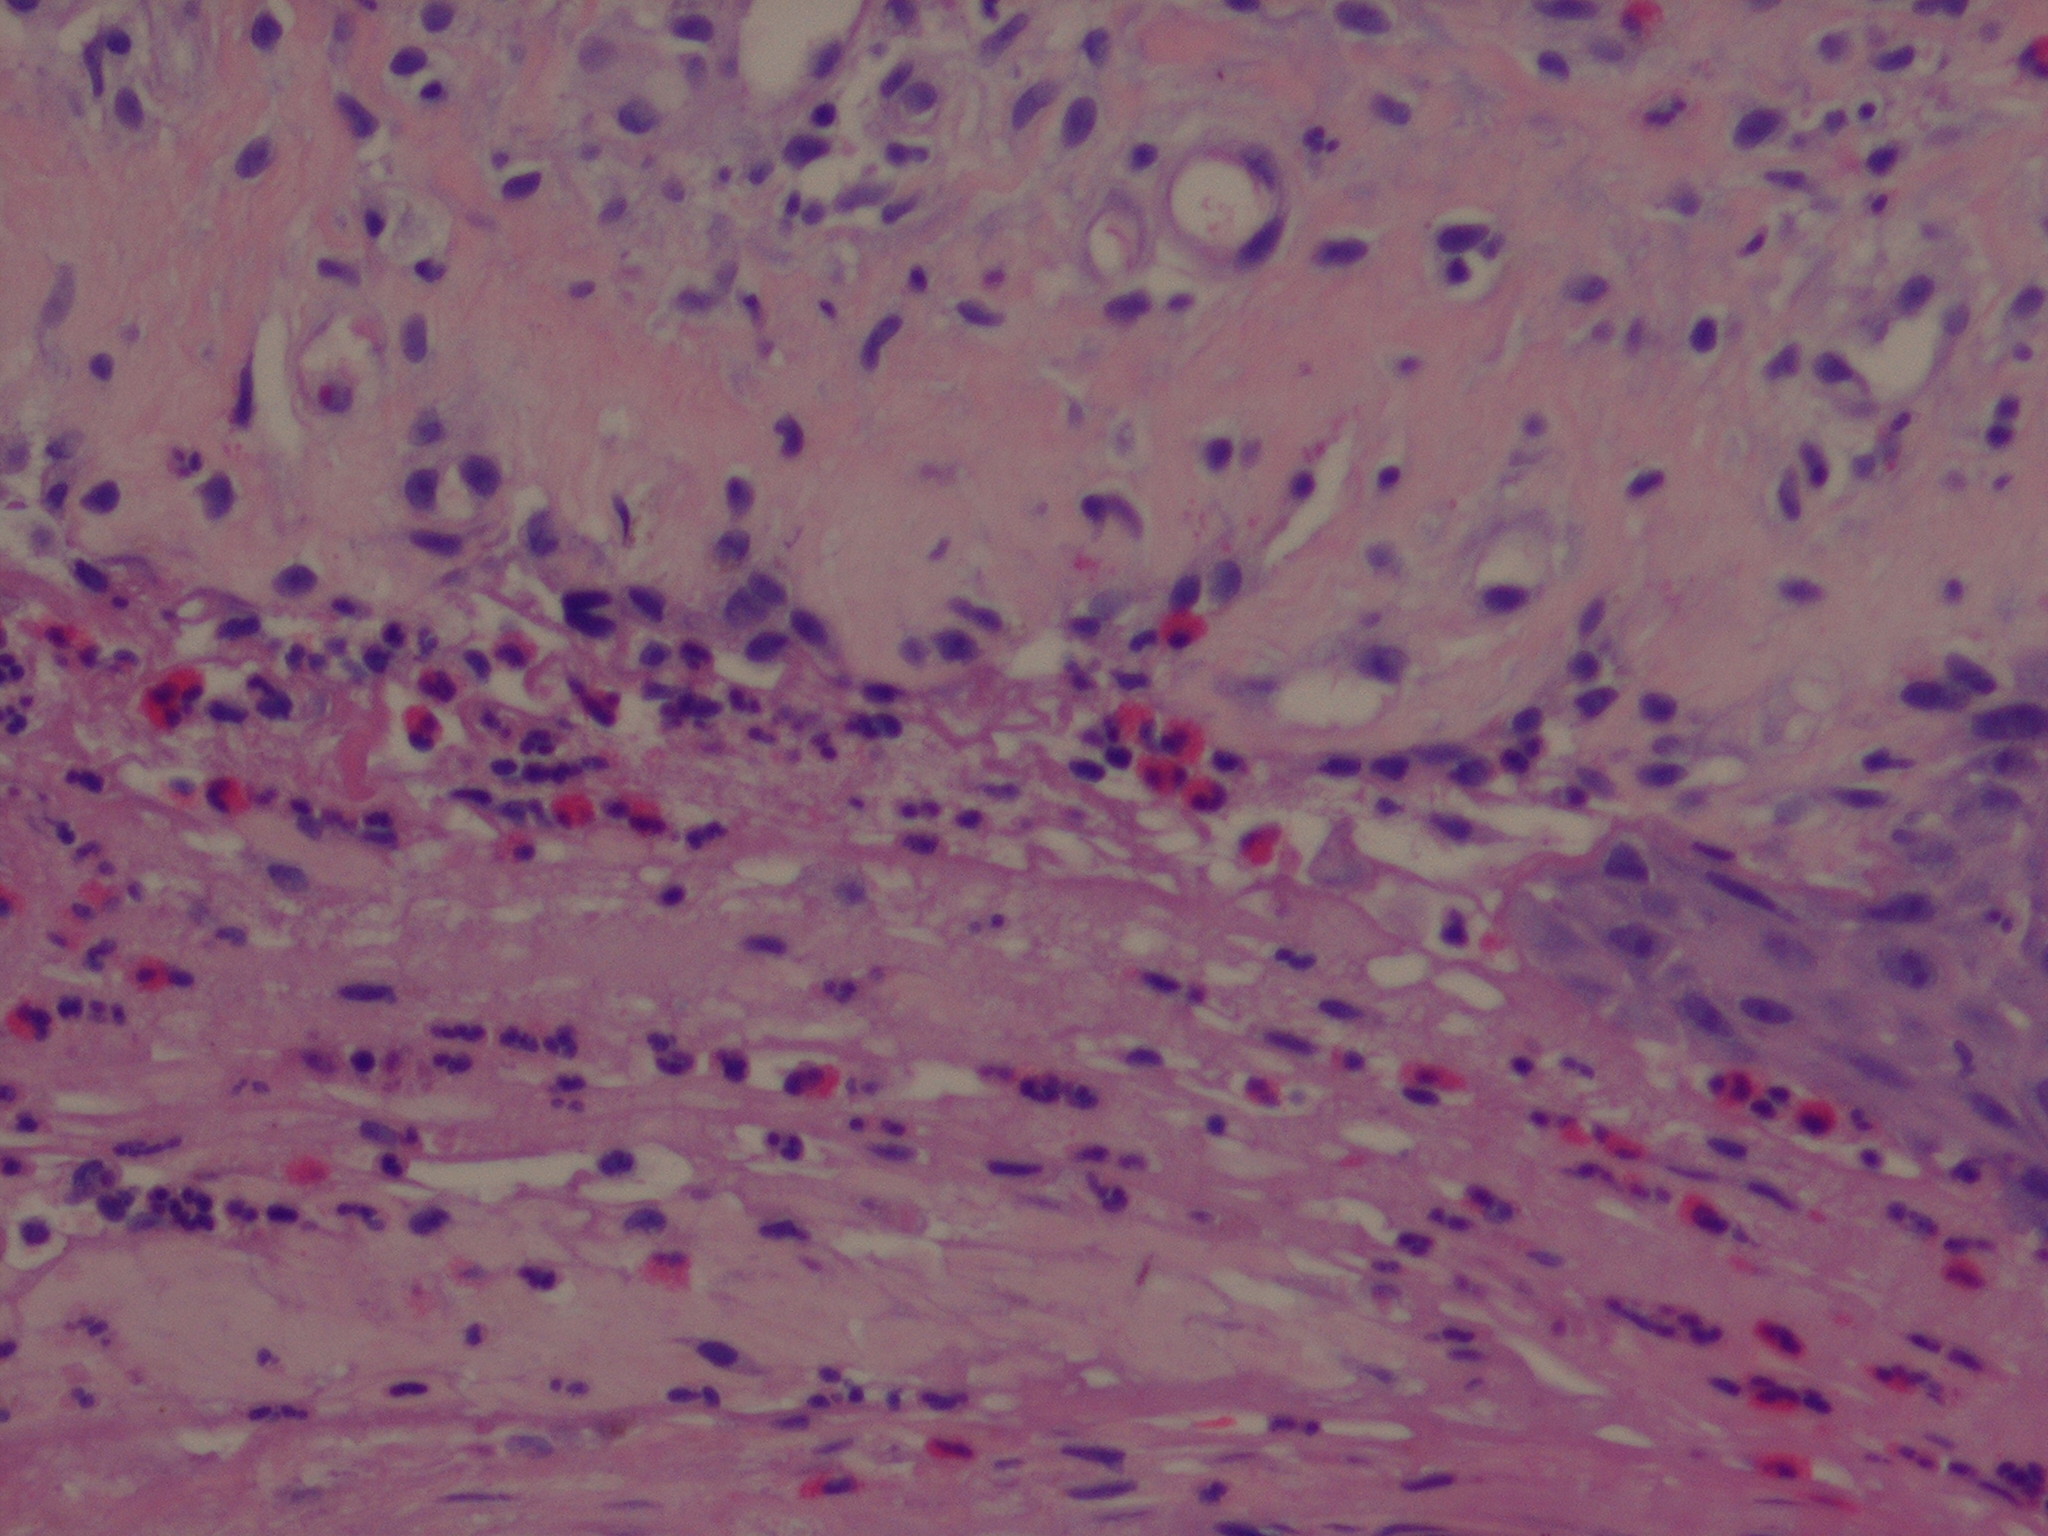

Histopathology.

In early lesions, papillary dermal edema in combination with a cell-poor or cell-rich perivascular lymphocytic and eosinophilic infiltrate is present. The blister arises at the dermal-epidermal junction . In the cell-rich pattern, which correlates clinically with blisters arising on erythematous skin , eosinophilic papillary abscesses may develop with numerous perivascular and interstitial eosinophils intermingled with lymphocytes and neutrophils in the superficial and deep dermis. Early lesions may have the histologic features of eosinophilic cellulitis (Well’s syndrome). Eosinophilic spongiosis may occur. The cell-poor pattem is observed

when blisters develop on relatively normal skin , in which there is usually a scant perivascular lymphocytic infiltrate with few eosinophils, some scattered throughout the dermis and others near the epidermis. The blister contains few inflammatory cells. Epithelial migration and regeneration may result in an intraepidermal split in older blisters. Similar to pemphigus vegetans, a hyperplasia of the epidermis, subepidermal bullae, and accumulations of eosinophils and lymphocytes may be seen.